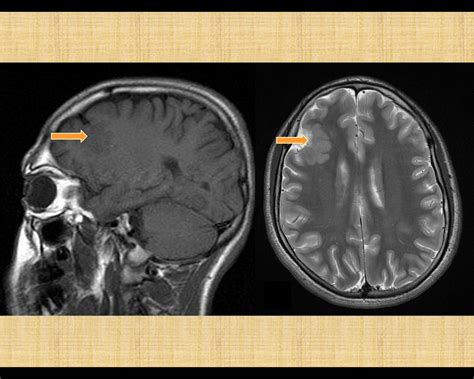

We are vaccinating patients ages 12+. Reducing carbs and replacing them with healthy fats can cause your body to enter a metabolic state known as ketosis. Vaccines, boosters & 3rd doses. This material must not be used for commercial purposes, or in any hospital or medical facil. A diet that can control epilepsy and stop seizu. Possible causes, signs and symptoms, standard treatment options and means of care and support. Frontal Lobe Epilepsy Causes, Symptoms, Diagnosis and Source: i0.wp.com

Epilepsy affects the central nervous systems and allows abnormal activity within the brain. We are vaccinating patients ages 12+. Frontal Lobe Epilepsy Causes, Symptoms, Diagnosis and Source: i0.wp.com